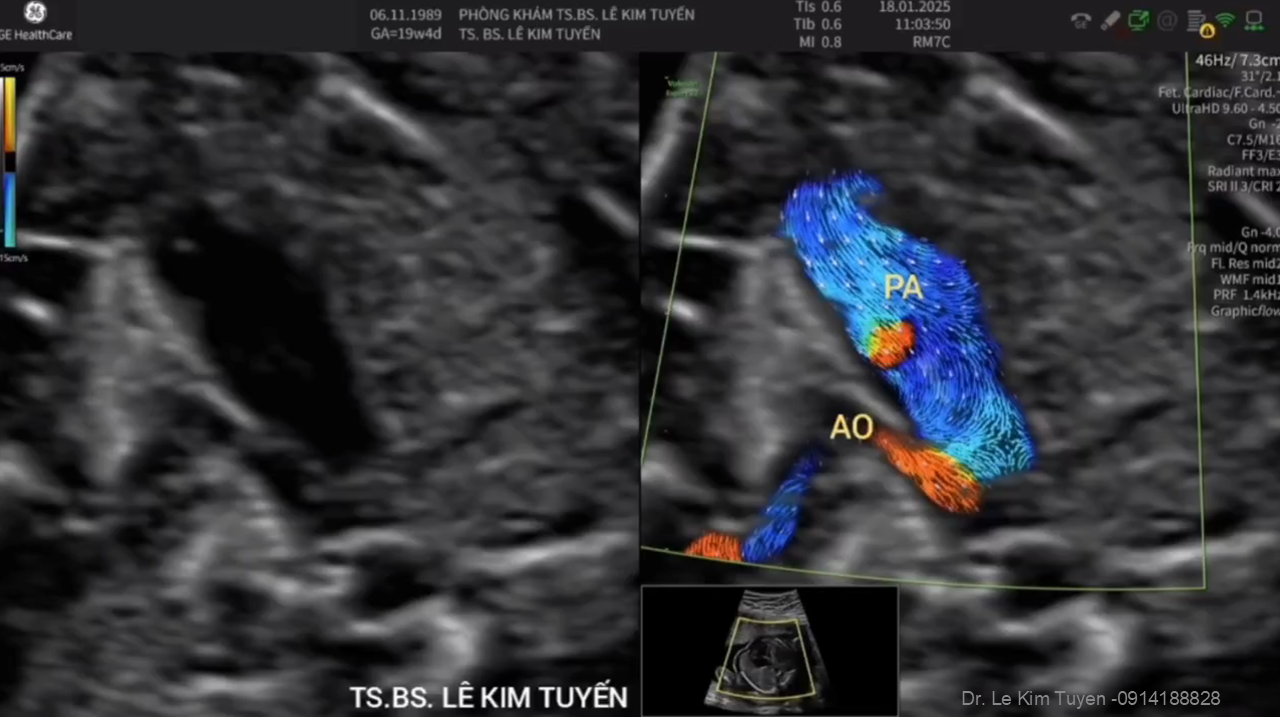

Áp dụng công nghệ Graphicflow trong phát hiện bệnh tim bẩm sinh cần cấp cứu sơ sinh

TS. BS. Lê Kim Tuyến